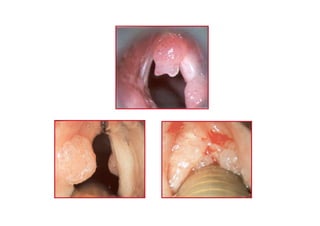

AnteriorAnterior komisskomissüürr caca

T1T1 glottikglottik larenkslarenks caca

T3T3 glottikglottik larenkslarenks caca